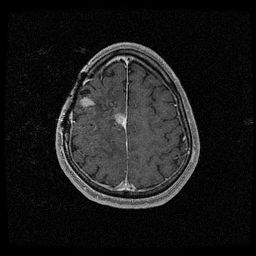

Abi pointed out that there are two lesions not just one.  The second lesion first showed up last month on the MRI and was bigger on this month’s MRI.  The doctor said he would treat both lesions at the same time, but there is a risk of increasing all my current deficits:  left side weakness, seizures and cognitive deficits. The tumor is growing fast enough, that the benefits outweigh the risks.

At the end of the day, at 3:00pm, Abi and I were really starting to drag and that’s when we met with the surgeon.  He said there are two lesions, and removing the main one would be a “chip shot.”  Abi and I just looked at him.  Then he explained that it would be very easy to remove.  Clearly he plays a lot of golf.  But, then he said the second lesion changes the whole story.  That it would not be easy to remove at all; it is right over the motor cortex, right about the left arm.  He thinks doing any surgery would just delay needed treatment by at least two weeks.  If I got another infection, it would delay it even longer.  So, his recommendation, in the end, was the same as the chemo doctor’s in the beginning, chemo plus radiation.